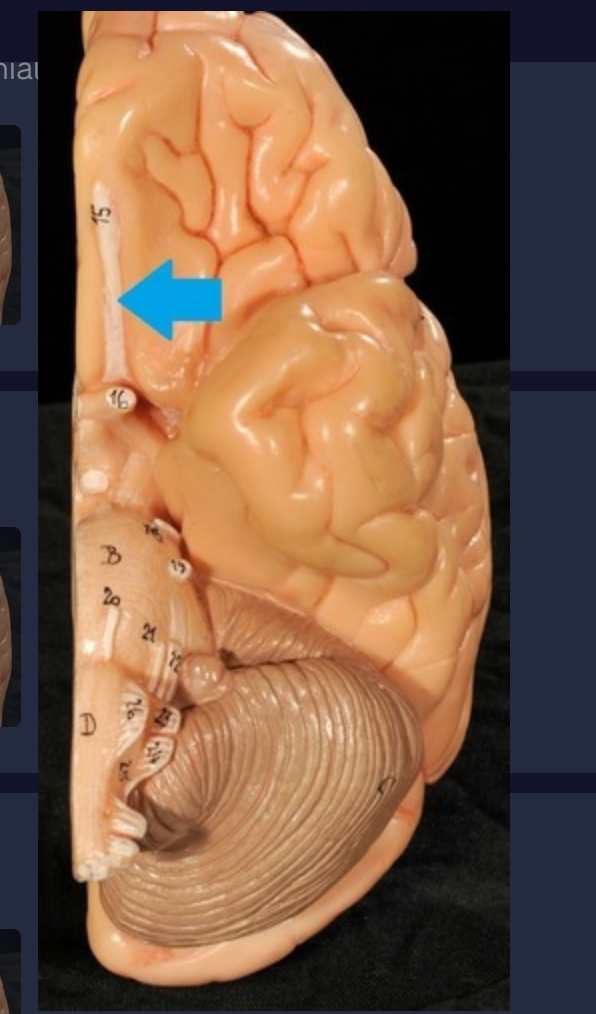

Longitudinal fissure

Cerebral cortex (gray matter)

Cerebral medulla (white matter)

Precentral gyrus

Postcentral gyrus

Central sulcus

Cerebellum

Corpus callosum

Diencephalon

Thalamus

3rd ventricle

Hypothalamus

Epithalamus (pink line)

Brain stem

Pons

Medulla oblongata

Choroid plexus of 3rd ventricle

Cerebral aqueduct (midrain)

4th ventricle

central canal